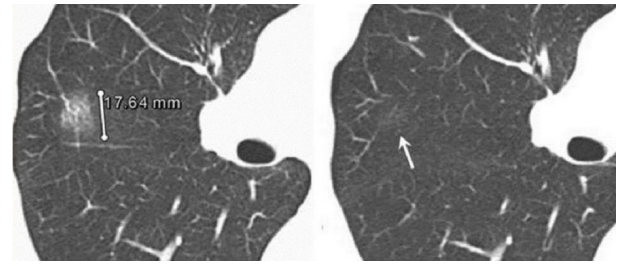

3、持续性与一过性GGO

一过性GGO指新发现的病灶绝大部分(40%-70%),患者治不治疗,均可自行消失。消失的时间一般在三个月以内,极少数甚至可以半年后才消失。而持续性GGO表现为持续存在半年及以上,定期复查不消失。

图四 间隔3个月复查后同一位置GGO消失